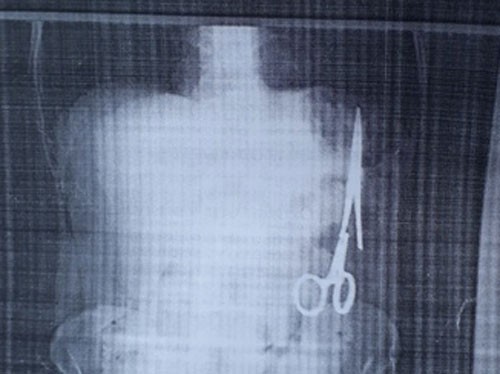

Chiếc kéo được cho là đã nằm trong bụng bệnh nhân 18 năm. Ảnh: TTXVN.

Đau nhói ở bụng sau một lần việc quá sức, ông Nhật vào Bệnh viện Gang thép Thái Nguyên khám. Kết quả siêu âm ngày 25/12 cho thấy trong ổ bụng của ông có một chiếc kéo dài khoảng 15 cm, được cho là chiếc panh chuyên dùng để mổ của ngành y. 2 ngày sau ông đến siêu âm tại Bệnh viện đa khoa Bắc Kạn, kết quả tương tự.

Theo ông Nhật, trừ lần phẫu thuật cách đây 18 năm, ông chưa phải vào viện mổ lần nào nữa. Khi đó là tháng 6/1998, ông bị tai nạn giao thông khiến ghi đông xe đâm vào mạng sườn, được chuyển từ bệnh viện huyện ra bệnh viện đa khoa tỉnh và được chỉ định phẫu thuật. Sau mổ, ông vẫn ăn uống và sinh hoạt bình thường.